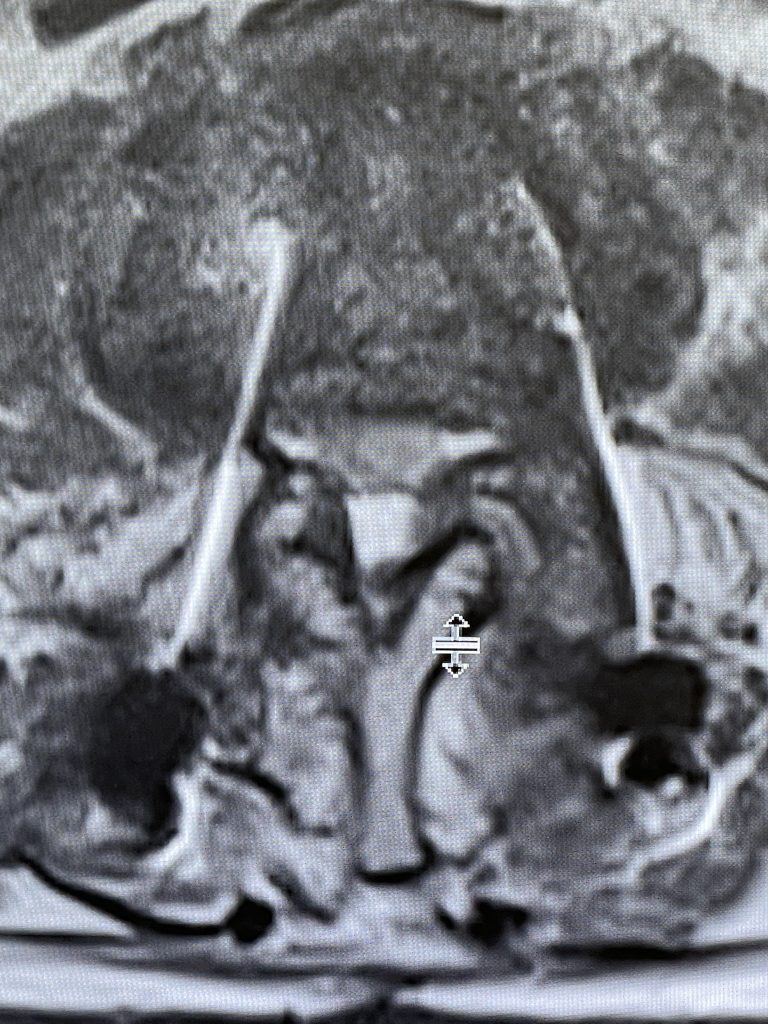

During the decompression we removed the inferior facets of L2 after the L3 screws were removed. This is a key maneuver in a revision decompression as it allows access to a dissection plane that allows the foramina and both L3 nerve roots to safely be decompressed. The L2 lamina is removed as well as a dissection plane at the inferior aspect of the bone is developed with an up biting curette. Because of her solid fusion it was only necessary to add new screws at L2 and L3 giving her a shorter construct and less potential stress at the next segment. Post operatively the patient did very well with resolution of leg pain and improved strength in her proximal leg strength. (Figure 3)

Figure 3. Post Op AP and lateral x-rays after L2-3 instrumented fusion